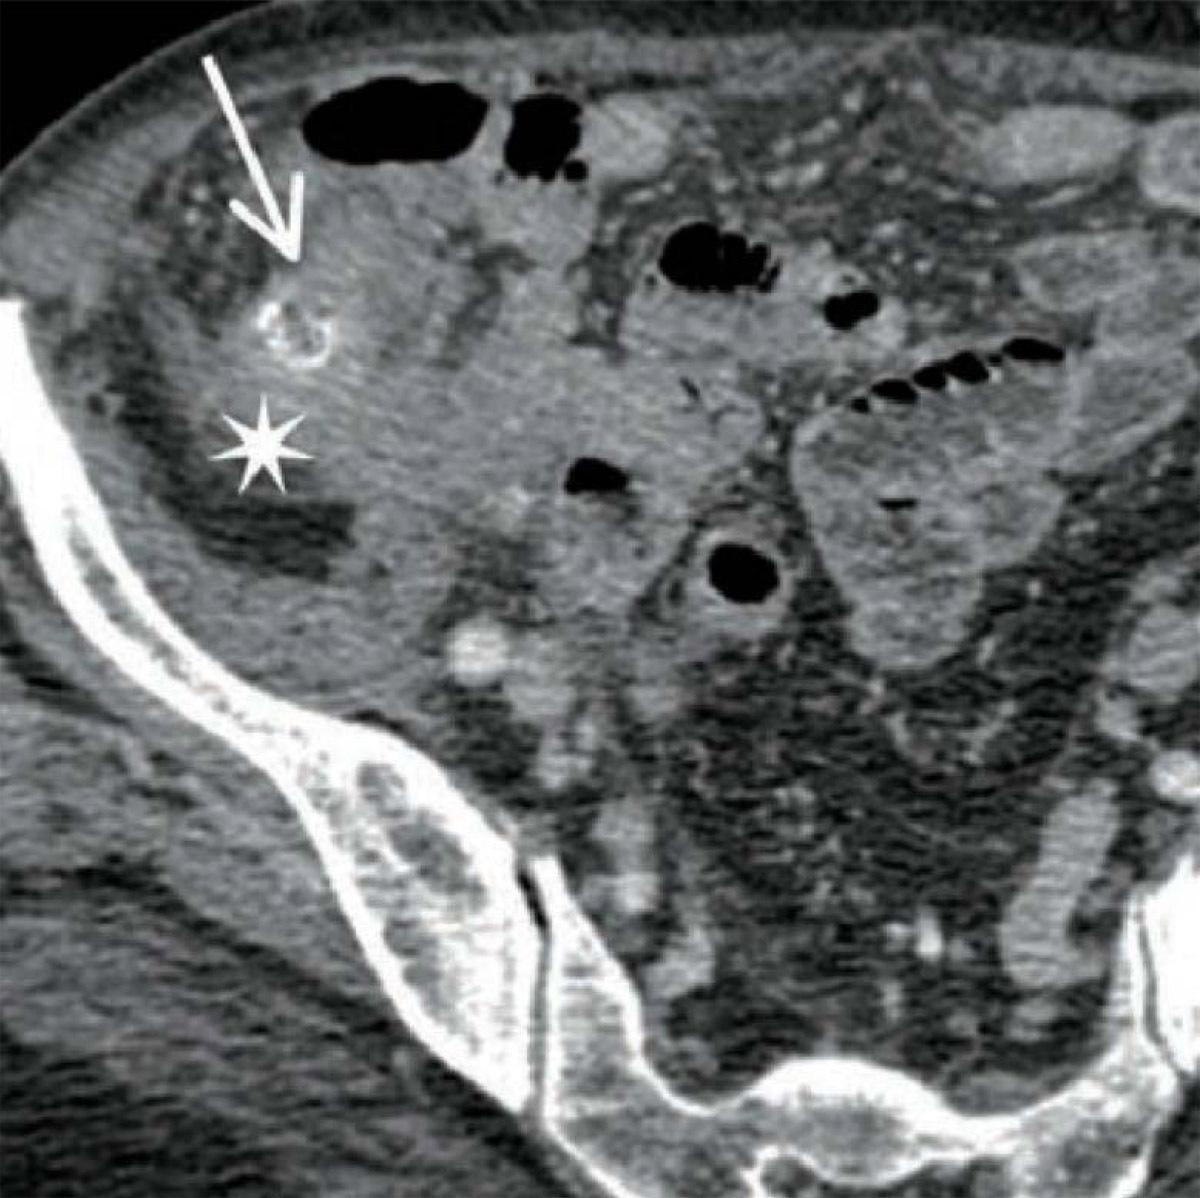

Quel est votre diagnostic ? Une TDM abdominopelvienne montrant un stercolithe Une TDM abdominopelvienne confirmant l’absence d’un appendice épaissi Une TDM abdominopelvienne normale Une IRM abdominale montrant un stercolithe Une IRM abdominale confirmant la présence d’un appendice épaissi OK Il s’agit d’une tomodensitométrie abdominopelvienne avec injection de produit de contraste chez une patiente ayant des douleurs diffuses avec syndrome infectieux biologique : l’appende est épaissi (tête de flèche) avec un stercolithe (flèche). Valider mes réponses